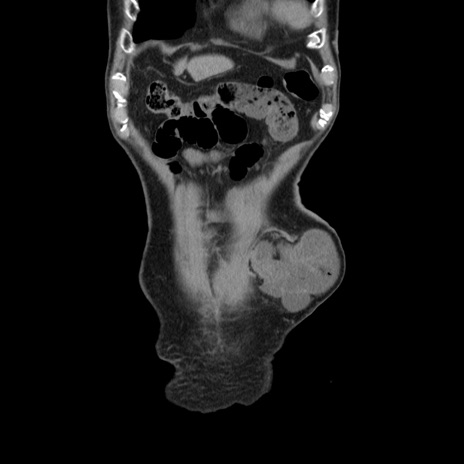

横断像

矢状断像

【症例】80歳代男性

【主訴】左側腹部痛、嘔吐

【現病歴】本日早朝より左腹部に痛みあり。昼頃嘔吐認めたため、救急要請。

【既往歴】直腸癌(Mile手術)、胆摘

【身体所見】意識清明、BT 35.9℃、BP 221/93mmHg、SpO2 97%(RA) 、腹部:左ストーマ周囲に限局性の腹部膨隆あり。 膨隆部自発痛・圧痛あり・軟。